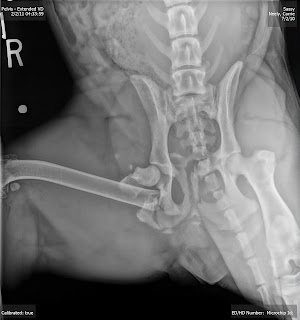

![]() |

| Side view of Sassy's repair |